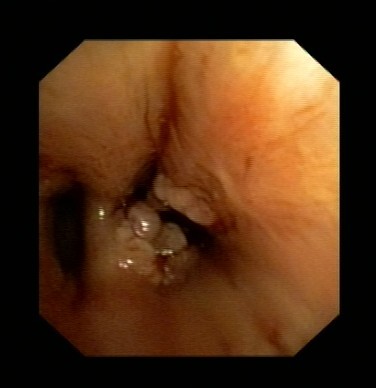

近日,呂先生有門診收入我呼吸科住院治療,全體醫(yī)護(hù)人員高度重視,認(rèn)真討論病情。我科吳主任仔細(xì)看過呂先生的CT片后,觀察到右下肺氣管內(nèi)異物,于是決定行支氣管鏡檢查。在氣管鏡室,吳主任給他做了支氣管鏡檢查,發(fā)現(xiàn)呂先生右下肺支氣管內(nèi)卡著一個黑黑的異物,由于時間太久,異物周圍已充血水腫,表面有膿苔及壞死物覆蓋,清除膿苔及壞死物后,可見異物被肉芽組織緊緊包埋。吳主任成功取出了呂先生氣管內(nèi)異物,并吸出了氣管內(nèi)膿性分泌物。呂先生咳嗽癥狀立刻改善,行氣管鏡檢查后第二天患者無咳嗽癥狀,順利出院。

圖表1氣管內(nèi)異物被壞死物包裹